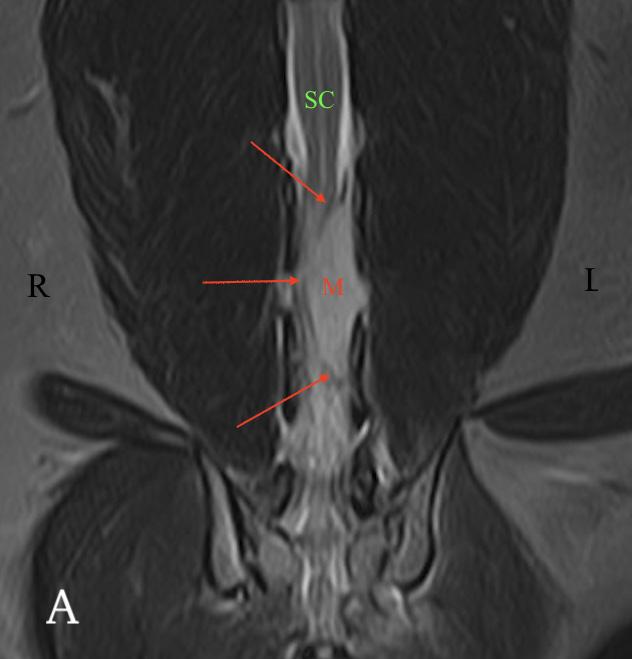

El examen neurológico evidenció paraparesia no ambulatoria y retraso en las reacciones posturales de ambas extremidades posteriores, más marcado en la extremidad posterior izquierda (EPI) (Fig.1). Los reflejos patelar, flexor y perineal estaban disminuidos y la nocicepción, intacta. El paciente presentaba parálisis de la cola con pérdida de nocicepción. La exploración de los pares craneales y las extremidades anteriores fue normal. No se detectó dolor espinal durante la evaluación. El examen neurológico fue compatible con una lesión localizada entre los segmentos espinales L4-S3.

Las pruebas diagnósticas realizadas incluyeron análisis de sangre, radiografía laterolateral de tórax y ecografía abdominal, sin resultar en alteraciones significativas. La serología frente al virus de la leucemia e inmunodeficiencia felina resultó positiva para esta última. En el estudio de resonancia magnética (RM; Fig. 2) de la región toracolumbosacra (Toshiba Vantage Elan 1.5 T: Adquisición de planos transversal, sagital y coronal ponderados en T1 pre y post-contraste intravenoso con gadolinio, así como planos ponderados en T2 y STIR) se cuentan 6 vértebras lumbares, lo cual es compatible con anatomía de transición en la región lumbar, como hallazgo incidental. En el lado izquierdo del canal vertebral, desde el tercio craneal de la vértebra L5 hasta el tercio caudal de la vértebra L6 se encuentra una lesión con aspecto alargado y de base ancha, con márgenes mal definidos e irregulares, distribución posiblemente extradural y/o intradural/extramedular, causando compresión severa de la médula espinal, que aparece desplazada hacia el lado derecho. En cuanto al patrón de intensidad de la señal, este fue hiperintenso de forma homogénea en las secuencias ponderadas en T2 e isointenso en las secuencias ponderadas en T1, con un realce homogéneo y focal en la región media de la vértebra L6. La lesión se extiende parcialmente en el foramen intervertebral izquierdo entre las vértebras L5 y L6 y se aprecia siringomielia leve, que puede ser un proceso secundario a la compresión de la médula espinal por parte de la lesión, más caudalmente a nivel lumbar.

Figura 2. Imágenes de RM postcontraste en las que se identifica una lesión de forma alargada y ancha en su base, con distribución posiblemente extradural y/o intradural/extramedular a nivel de la vértebra L6 (flechas rojas). (A) Secuencia dorsal en STIR. (B) Secuencia transversal en T2. Nótese la compresión severa a la que es sometida la médula espinal (flecha verde). (C) Secuencia transversal en T1 precontraste. (D) Secuencia transversal en T1 postcontraste. M: masa; SC: médula espinal; R: derecha; L: izquierda.